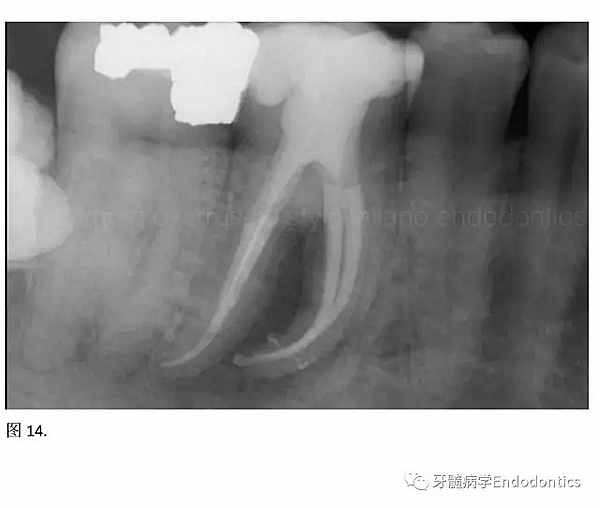

開髓后預(yù)敞、探查根管、建立直線通路是根管機(jī)械預(yù)備的第一步。在這些階段中,醫(yī)生可能會(huì)經(jīng)常遇到一些困難。這些難題包括器械折斷、臺(tái)階形成、根管歧坡或根管拉直、帶狀穿孔、根尖穿孔、根尖肘形、根尖堵塞。所有這些錯(cuò)誤可導(dǎo)致根管系統(tǒng)清潔不完善從而降低牙髓治療成功率。

結(jié)論:本文的目的是描述一種旨在優(yōu)化根管根尖部分預(yù)備的預(yù)敞技術(shù)。根管頸部或冠方的早期預(yù)敞對(duì)于減少初尖銼直徑和根尖部根管直徑之間的差異至關(guān)重要。大量研究表明,手用或機(jī)用器械預(yù)敞根管能顯著減少器械折斷的發(fā)生率。下一篇文章將描述如何建立可重復(fù)的引導(dǎo)路徑。而引導(dǎo)路徑是指鎳鈦器械可沿著光滑根管壁輕易地滑行至工作長度的通路。